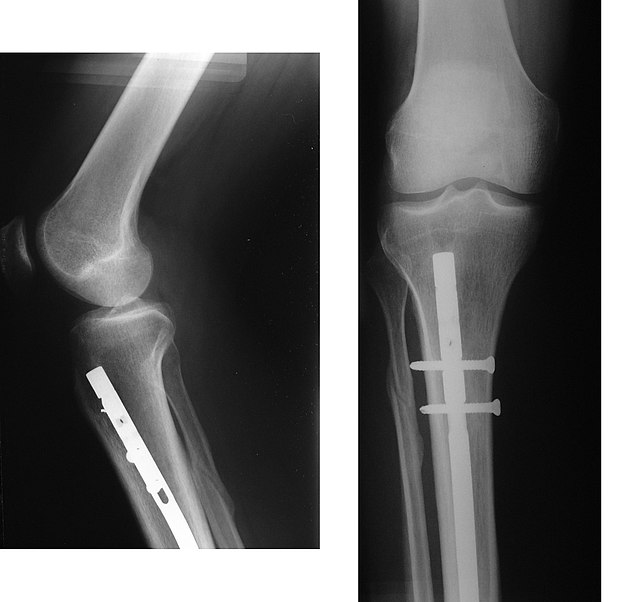

2023-01-15 Появление интрамедуллярного стержня произвело революцию в лечении переломов длинных костей.Хотя эта техника существовала веками, своего нынешнего статуса она достигла только во второй половине 20 века.Путь к успеху не всегда был легким, так как к технике относились скептически.